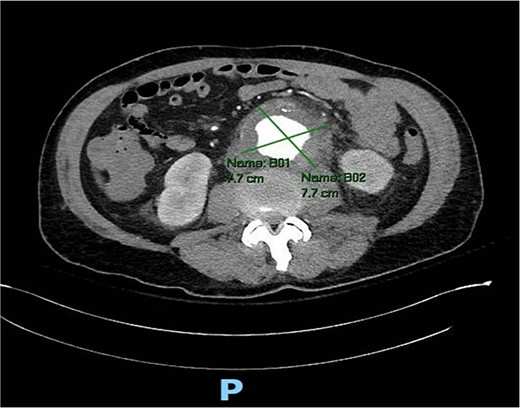

A 56-year-old male with no reported past medical history and a 70 pack year smoking history presented with a chief complaint of lower abdominal pain and body aches. On presentation, the patients white blood cell count (WBC) was 39.6 and procalcitonin was 43.4. Blood cultures were drawn and demonstrated P. mirabilis bacteremia. Computed tomography (CT) abdomen/pelvis was performed as well as ultrasound (US) of scrotum demonstrating a complex fluid collection within scrotal sac that was determined to be a scrotal wall abscess. The patient was started on a course of Unasyn and Urology promptly took him to the operating room (OR) for incision and drainage. Vascular surgery was consulted due to an incidental finding of an abdominal aortic aneurysm on CT measuring 4.7 × 4.6 cm (Figs 1 and 2). The patient was evaluated by the vascular surgery team following his urological procedure and denied any history of abdominal pain or back pain. Physical exam was largely unremarkable however the patient’s bilateral toes were noted to have blue discoloration with motor and sensation intact. Outpatient follow up with routine US scans for the AAA was recommended. Ankle brachial index (ABI) as well as an echocardiography was ordered to further work up the patient’s dusky toes. On Day 2 of hospitalization, ABIs returned showing severe peripheral vascular disease (PVD) and the echocardiography ruled out endocarditis. At this time an angiogram was planned to further the patient’s PVD workup however this was deferred as the patient remained septic with a WBC of 30. Over the course of the next few days the patient refused antibiotics and remained septic with a WBC in the 20s. At this time his toes quickly deteriorated from dusky to dry gangrene. On Day 8 of hospitalization the patient remained septic and was now complaining of new onset mid-abdominal pain. Emergent CT showed AAA was now 7.7 × 7.8 cm with periaortic fat stranding concerning for impending rupture (Figs 3 and 4). The patient was taken emergently to the OR for open repair. Upon visualization, the abdominal aortic aneurysm was clearly infected with signs of impending rupture on the left lateral wall and purulent material including infected thrombus. Tissue was cultured however showed no growth, likely due to the fact that the patient had been on antibiotic therapy for a week at this time. Reconstruction with an aorto-biiliac bypass using rifampin-soaked dacron graft was performed. A piece of omentum was mobilized over the graft and the retroperitoneum was closed over it. The abdomen was left open for a return to the OR for a second look which showed no concerns for bowel ischemia, worsening infection or bleeding. On post-op Day 5 the patient was extubated, off pressor support, and transferred to the floor. The patient’s postoperative course was unremarkable except for bilateral toes demarcating to dry gangrene.

Axial CT angiography of the abdomen and pelvis demonstrating 7.7 cm AAA with fat stranding.